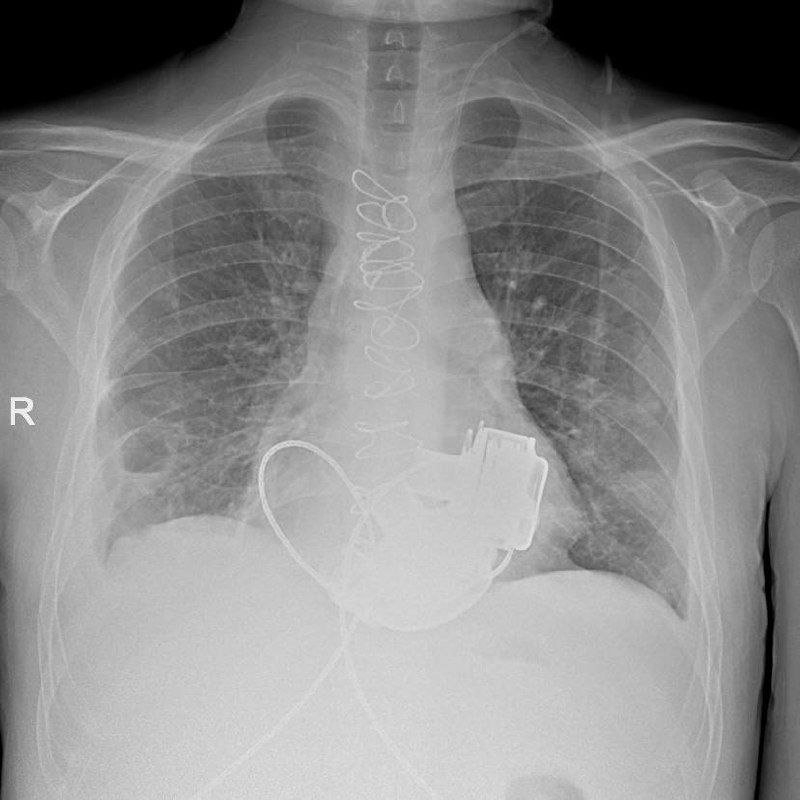

В Мариинской больнице готовится к выписке уникальный пациент, который с недавних пор живет без пульса. Как сообщает учреждение в своем телеграм-канале, в конце ноября 2025 пациенту впервые в России имплантировали сразу два искусственных желудочка сердца. Когда мужчина поступил в больницу, показатели работы его сердца были такими, "будто человек уже не жив, а мертв". При этом из-за ряда осложнений трансплантация целого сердца была невозможной. Главный врач больницы Игорь Реутский принял решение об имплантации искусственных желудочков. Операция продолжалась около 4 часов.

Рентген пациента с искусственными желудочками сердца. Фото: Телеграм-канал Маринской больницы